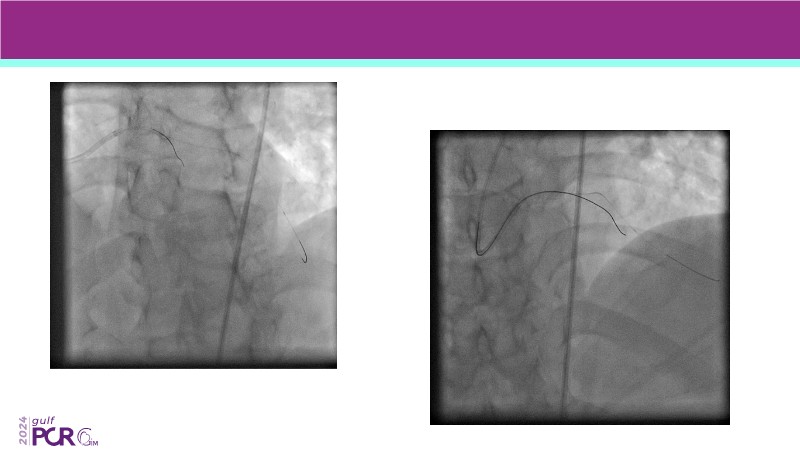

- To discover your next gen complex PCI toolkit with thin strut platforms and dedicated stenting solutions for managing side branch and long diffused lesions

- To learn about the novel Myval THV technology, its key features, procedural and clinical benefits and learn about the clinical data in a vast cohort of patient population